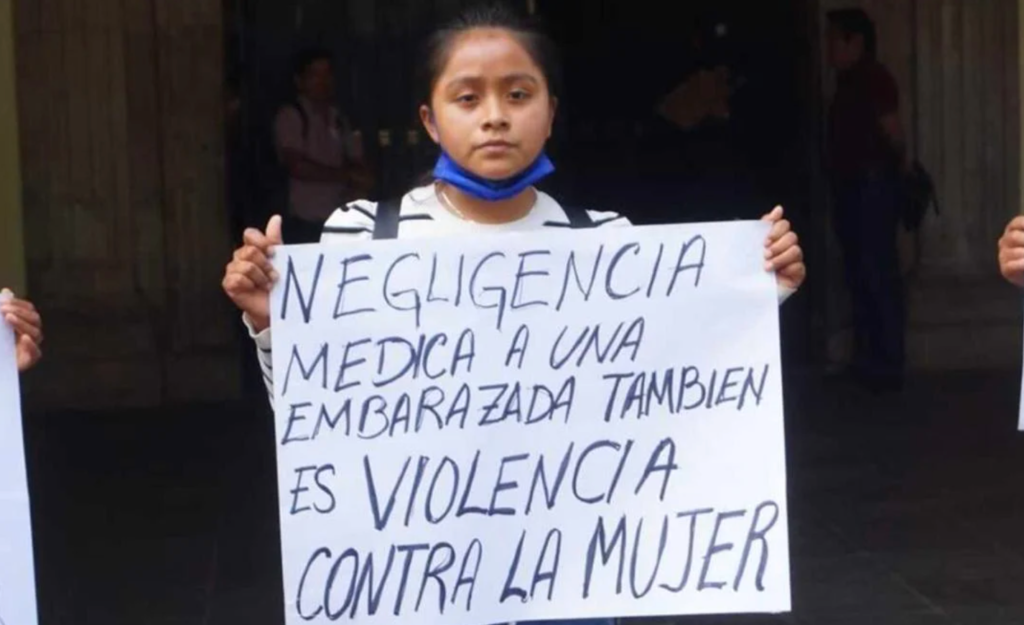

Colectivas denuncian que falta de medicamentos y personal limita abortos seguros en Oaxaca

Oaxaca de Juárez, Oax.– Integrantes de colectivas feministas agrupadas en el movimiento Marea Verde Oaxaca denunciaron que en los centros de salud y hospitales públicos del estado persisten graves carencias de insumos, medicamentos e infraestructura, lo que impide garantizar abortos seguros y gratuitos, a pesar de que el procedimiento está despenalizado en la entidad desde […]